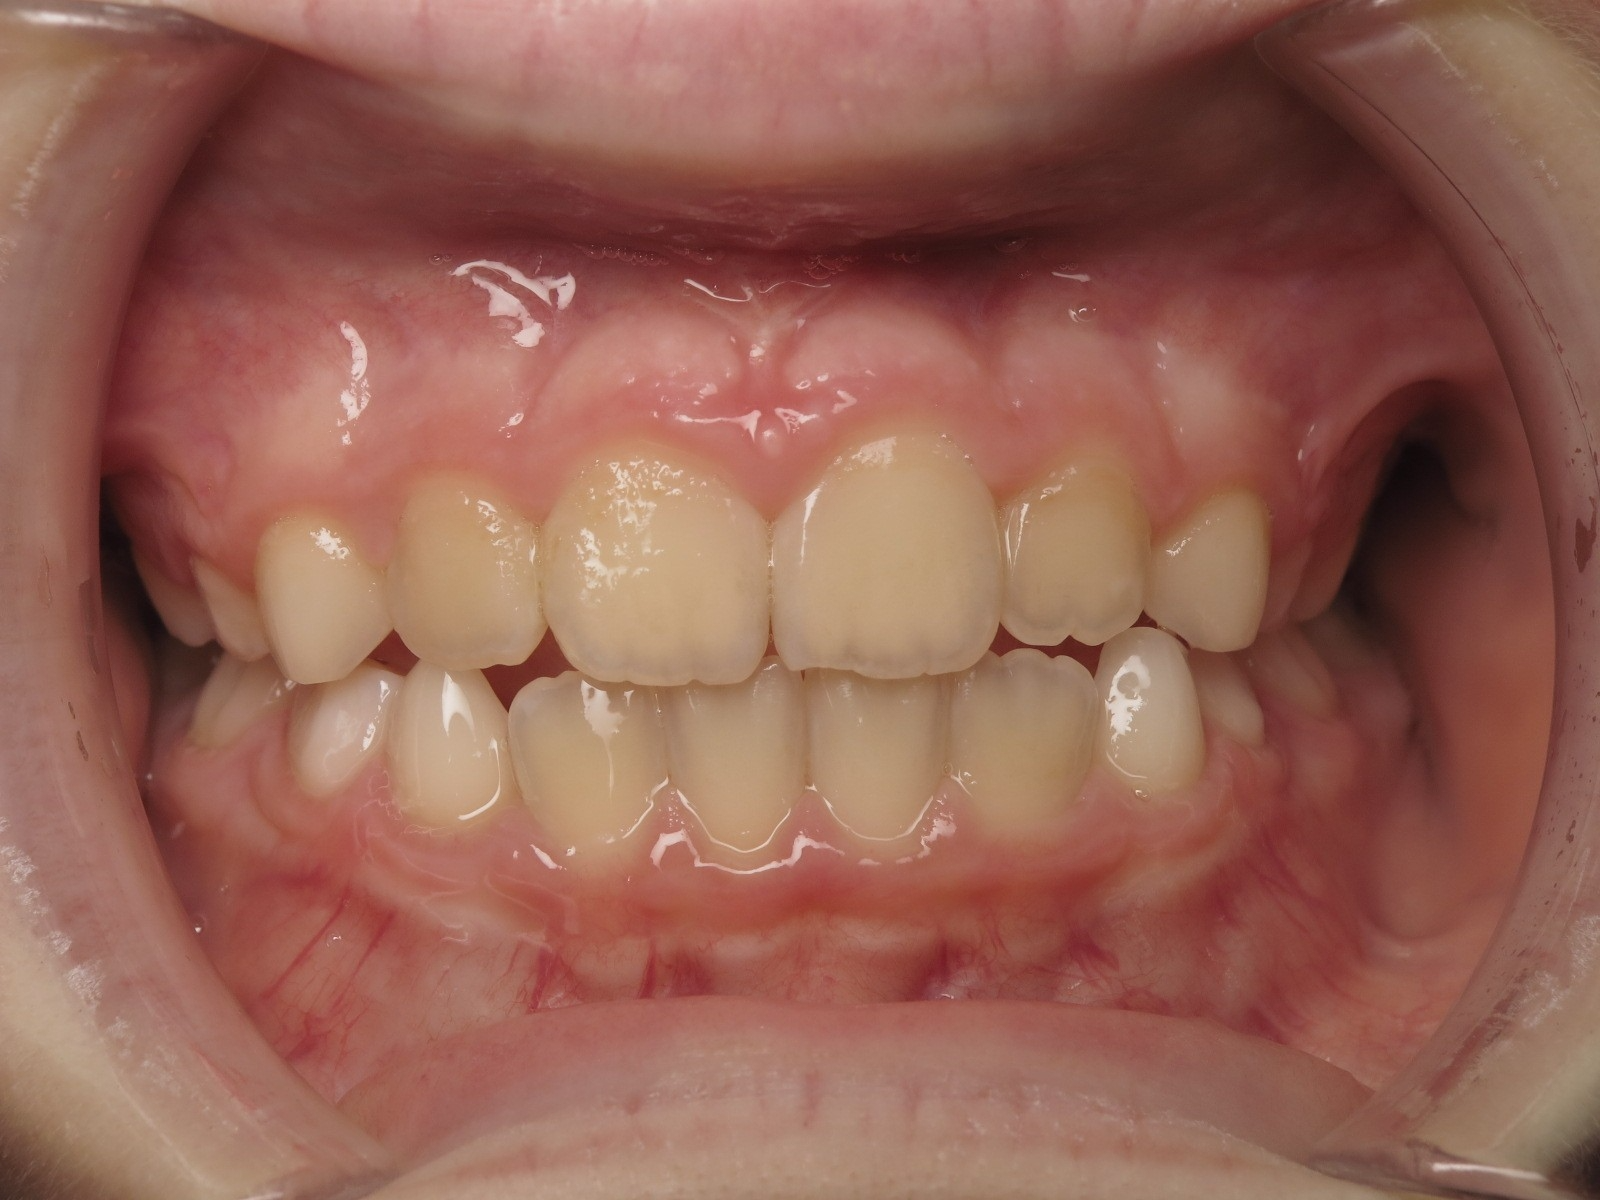

18 béance inversé droit 4 ans

Sélectionnez les différentes étapes du traitement pour comparer et analyser la dentition du cas clinique.

inversion des dents postérieur et espace entre l'arcade du haut et du bas (béance)

appareillage mobile pendant 3 ans

sectionnel multibagues pendant 8 mois

surveillance évolution de la dentition